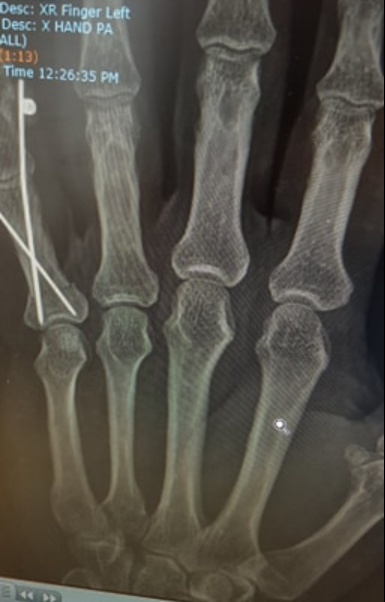

I see that it's your left hand.... Lucky for you hey?? 😜

Thanks, mate. This is the least objectionable photo.

Lol, no, I broke my pinky. It was off in the whole wrong direction for a while.

Didn't want to post a pic as it's pretty confronting :)

Phew, I was worried it was something serious...Just a pinky pointing west huh? Must have tickled a bit.